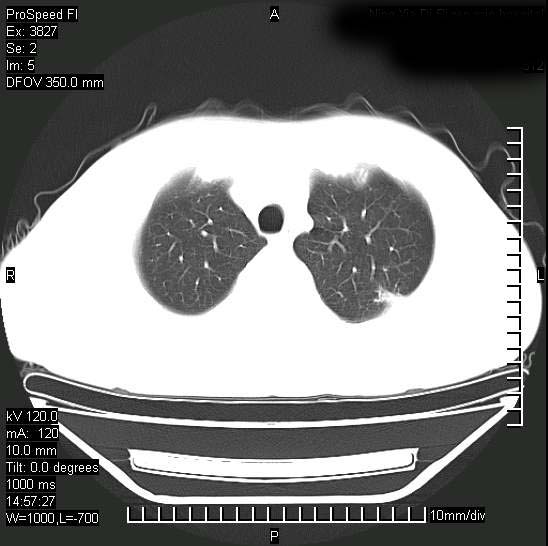

男性,一月前出现右侧肋区疼痛,较剧烈,干咳,无发热,自诉使用抗炎药后缓解,几天前又出现左侧剧烈疼痛,

发热,体温38。9,今天ct,考虑左侧包裹性脓胸,胸腔积液,右上中肺小斑片影,结核/炎症?胸水未见恶性细胞。

支持:脓胸!并双肺继发性肺结核!

脓胸没问题,肺内还可见感染灶,感觉不像是结核性病变.